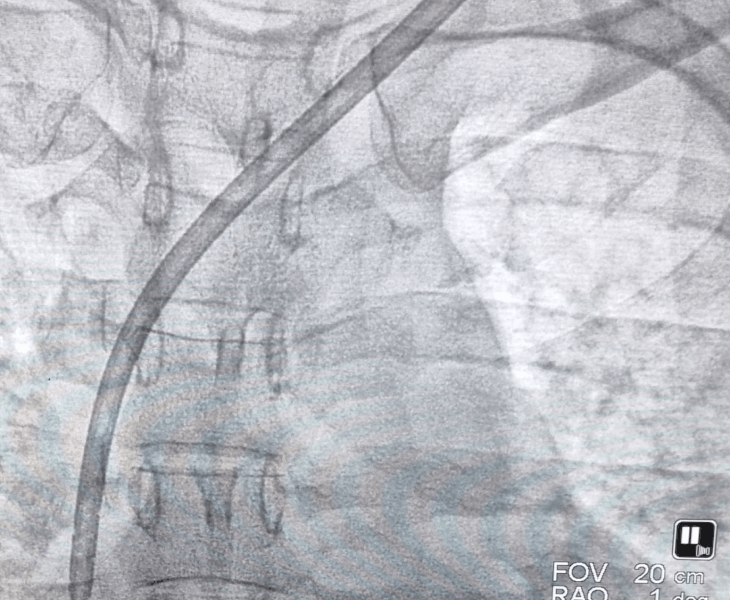

- Fluoroscopy guidance to position the catheter tip accurately in the central vein.

- Flow check to confirm both lumens function well for dialysis.